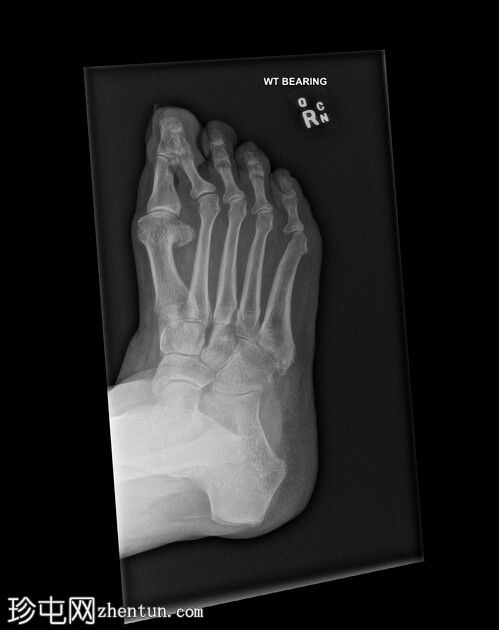

X线片

斜位片

第二趾交叉畸形,跖趾关节伸展,足趾内旋,压在相邻拇趾背侧。

第二趾内旋,压在拇趾上。患者有长期穿高跟鞋的病史。